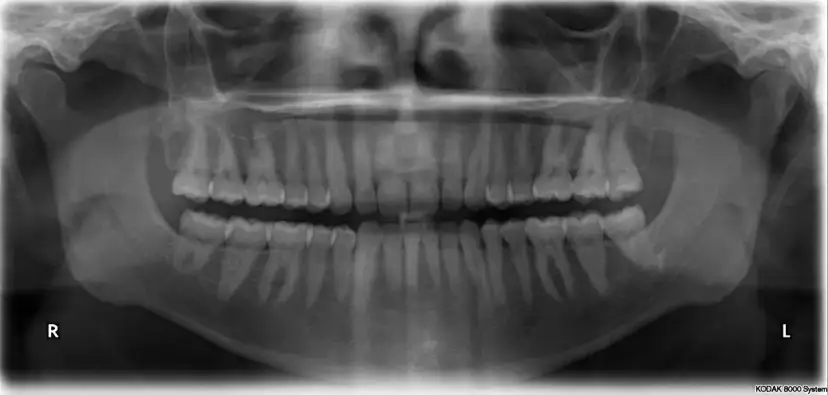

Pantomogram zębów: kompleksowy przewodnik. Dowiedz się, co widać na zdjęciu, jak przebiega badanie, czy jest bezpieczne i ile kosztuje. Rozwiej obawy!